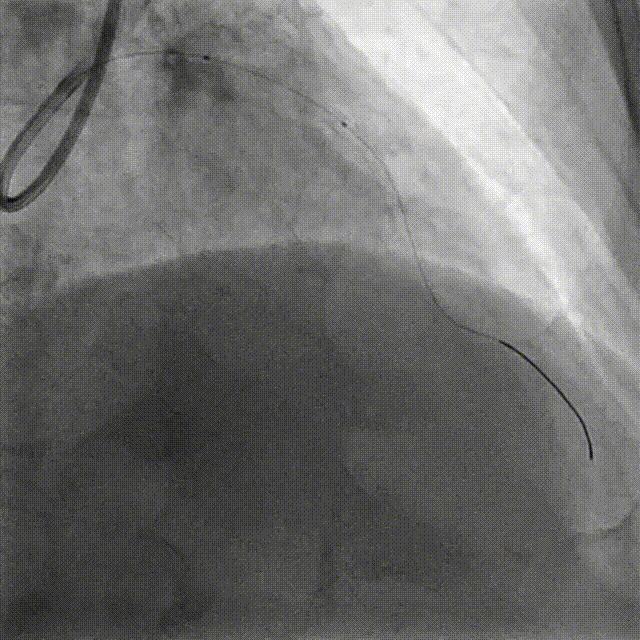

PCI-RCA TR, 7F JR4.0 ROTA with 2.0mm burr

Angiography post-ROTA